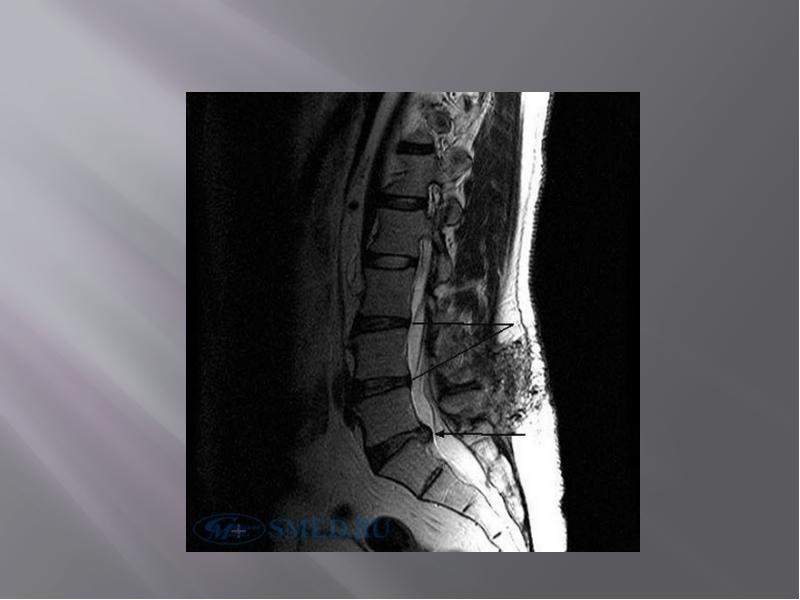

- 48. МРТ – исследование в большинстве случаев позволяет выявить: МРТ – исследование